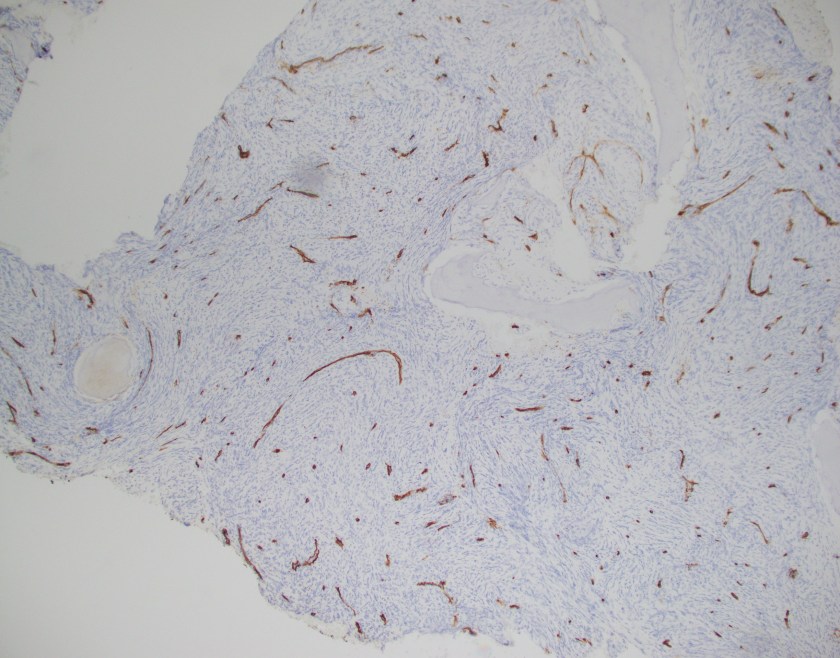

The CBC demonstrated severe anemia and mild leukopenia. The peripheral blood smear showed numerous acanthocytes and poikilocytosis shown below.

Acanthocytes, or spur cells, are spiculated red cells with a few projections of varying size and surface distribution that can be seen in a variety of clinical conditions including CGD with McLeod red cell phenotype. Other conditions include (but are not limited to) neuroacanthocytosis, malnutrition states, infantile pyknocytosis, (Lu) null Lutheran phenotype, hypothyroidism, myxedema, and Zieve syndrome. Acanthocytes should be distinguished from echinocytes, or burr cells, that also demonstrate multiple small projections but these are uniformly distributed on the red cell surface.

The prominent acanthocytosis seen in McLeod syndrome is thought to be due to an imbalance of the number of lipids in the inner layer relative to the outer layer. Related to this phenomenon is McLeod neuroacanthocytosis syndrome, a disorder with neurologic manifestations including movement disorders, cognitive alterations, and psychiatric symptoms. Although our patient did not exhibit these symptoms, McLeod neuroacanthocytosis syndrome is known to start in early to middle adulthood and the patient will need to be monitored for the onset of neurologic sequelae.